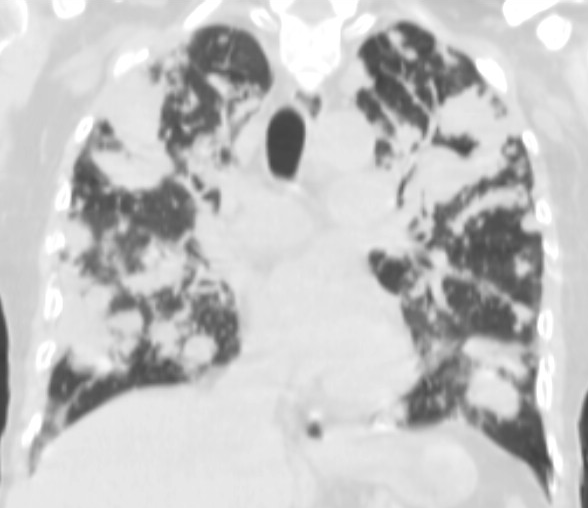

4: Miliary pattern: sarcoidosis, CT, lung window. Axial image and sagittal reformat.

A 67 year old female suffering from COPD. Bilateral rough branching interstitial widening and patchy, miliary nodules with perihilar dominance along the bronchovascular fibres and the fissures.